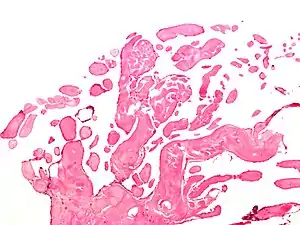

| Micrograph of a papillary fibroelastoma, a benign tumor of heart valves. H&E stain. | |

A subset of the primary tumors of the heart are tumors that are found on the valves of the heart. Tumors that affect the valves of the heart are found in an equal distribution among the four heart valves.[1] The vast majority of these are papillary fibroelastomas. Primary tumors of the valves of the heart are more likely to occur in males. While most primary tumors of the valves of the heart are not malignant, they are more likely to have symptoms related to the valve, including neurologic symptoms and (in a few cases) sudden cardiac death.